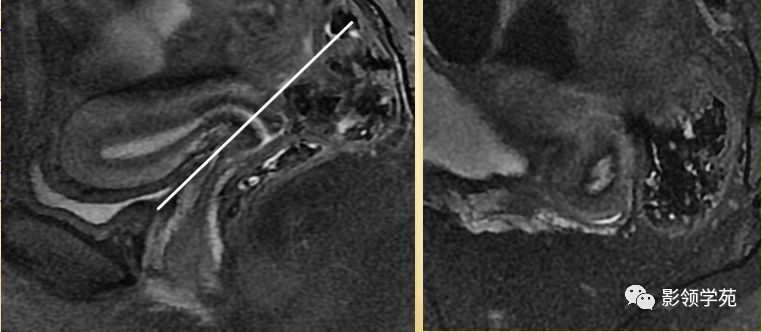

宫颈癌MRI表现

宫颈癌可表现为类圆形或不规则形肿块,在T2WI上表现为均匀或欠均匀的高信号,与正常宫颈基质及宫旁脂肪形成良好的自然对比。

MRI

- Ⅰ期肿瘤:侵犯宫颈基质,T2WI等信号肿块,宫颈管扩大及宫颈纤维基质中断

- Ⅱ期肿瘤:宫颈增大,宫旁肿块或宫旁脂肪组织内出现异常信号的粗线状影

- Ⅲ期肿瘤:侵犯至阴道下部,外延至盆壁,或出现肾积水。

- Ⅳ期肿瘤:膀胱壁或直肠壁低信号中断,膀胱壁或直肠壁增厚或腔内肿块。

Ⅰ期

IIA期

IIB期